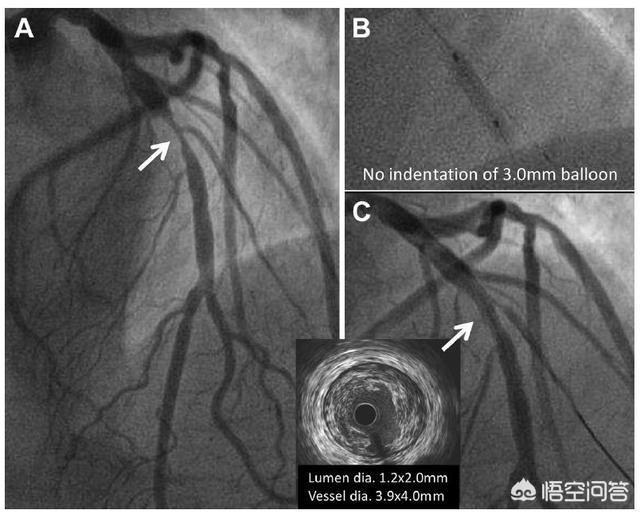

2、画像診断の結果、冠動脈病変の狭窄の程度が50%から70%である:このような場合、ステントは入れるか入れないかのクリティカル病変に属し、ケースバイケースで分析すべきである。活動時の胸痛がそれぞれ5分程度続くなど明らかな狭心症状があり、安静にしていれば軽快し、ニトログリセリンが有効であれば、このような患者にもステント留置が勧められる。明らかな狭心症状がない場合は、アスピリン、メトプロロール、スタチンなどの内服薬による保存的治療が可能である。より確実な方法は、血管内画像診断である冠動脈超音波(IVUS)検査や冠動脈内光断層撮影(OCT)検査を再度行い、狭窄の程度を正確に分析することである。 これら2つの検査の結果、狭窄が70%に達していれば、やはりステント留置が推奨される。

下の画像は、冠動脈の光断層撮影(OCT)スキャンである。